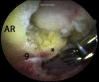

The modified mid-anterior portal is a utilitarian hip arthroscopy working portal that permits dual-portal comprehensive surgery for femoroacetabular impingement and related chondrolabral procedures without the need for interportal exchange. Its distal location facilitates labral reparative and reconstructive procedures while minimizing iatrogenic acetabular chondral damage. The relatively lateral location permits instrument navigation not only along the anterosuperior acetabular rim and anterolateral proximal femur typically required for acetabuloplasty and femoroplasty but even to the posterior regions of the hip in cases of global pincer femoroacetabular impingement and posterior extensions of cam morphology and the anteromedial proximal femur while avoiding direct injury to the lateral femoral cutaneous nerve.